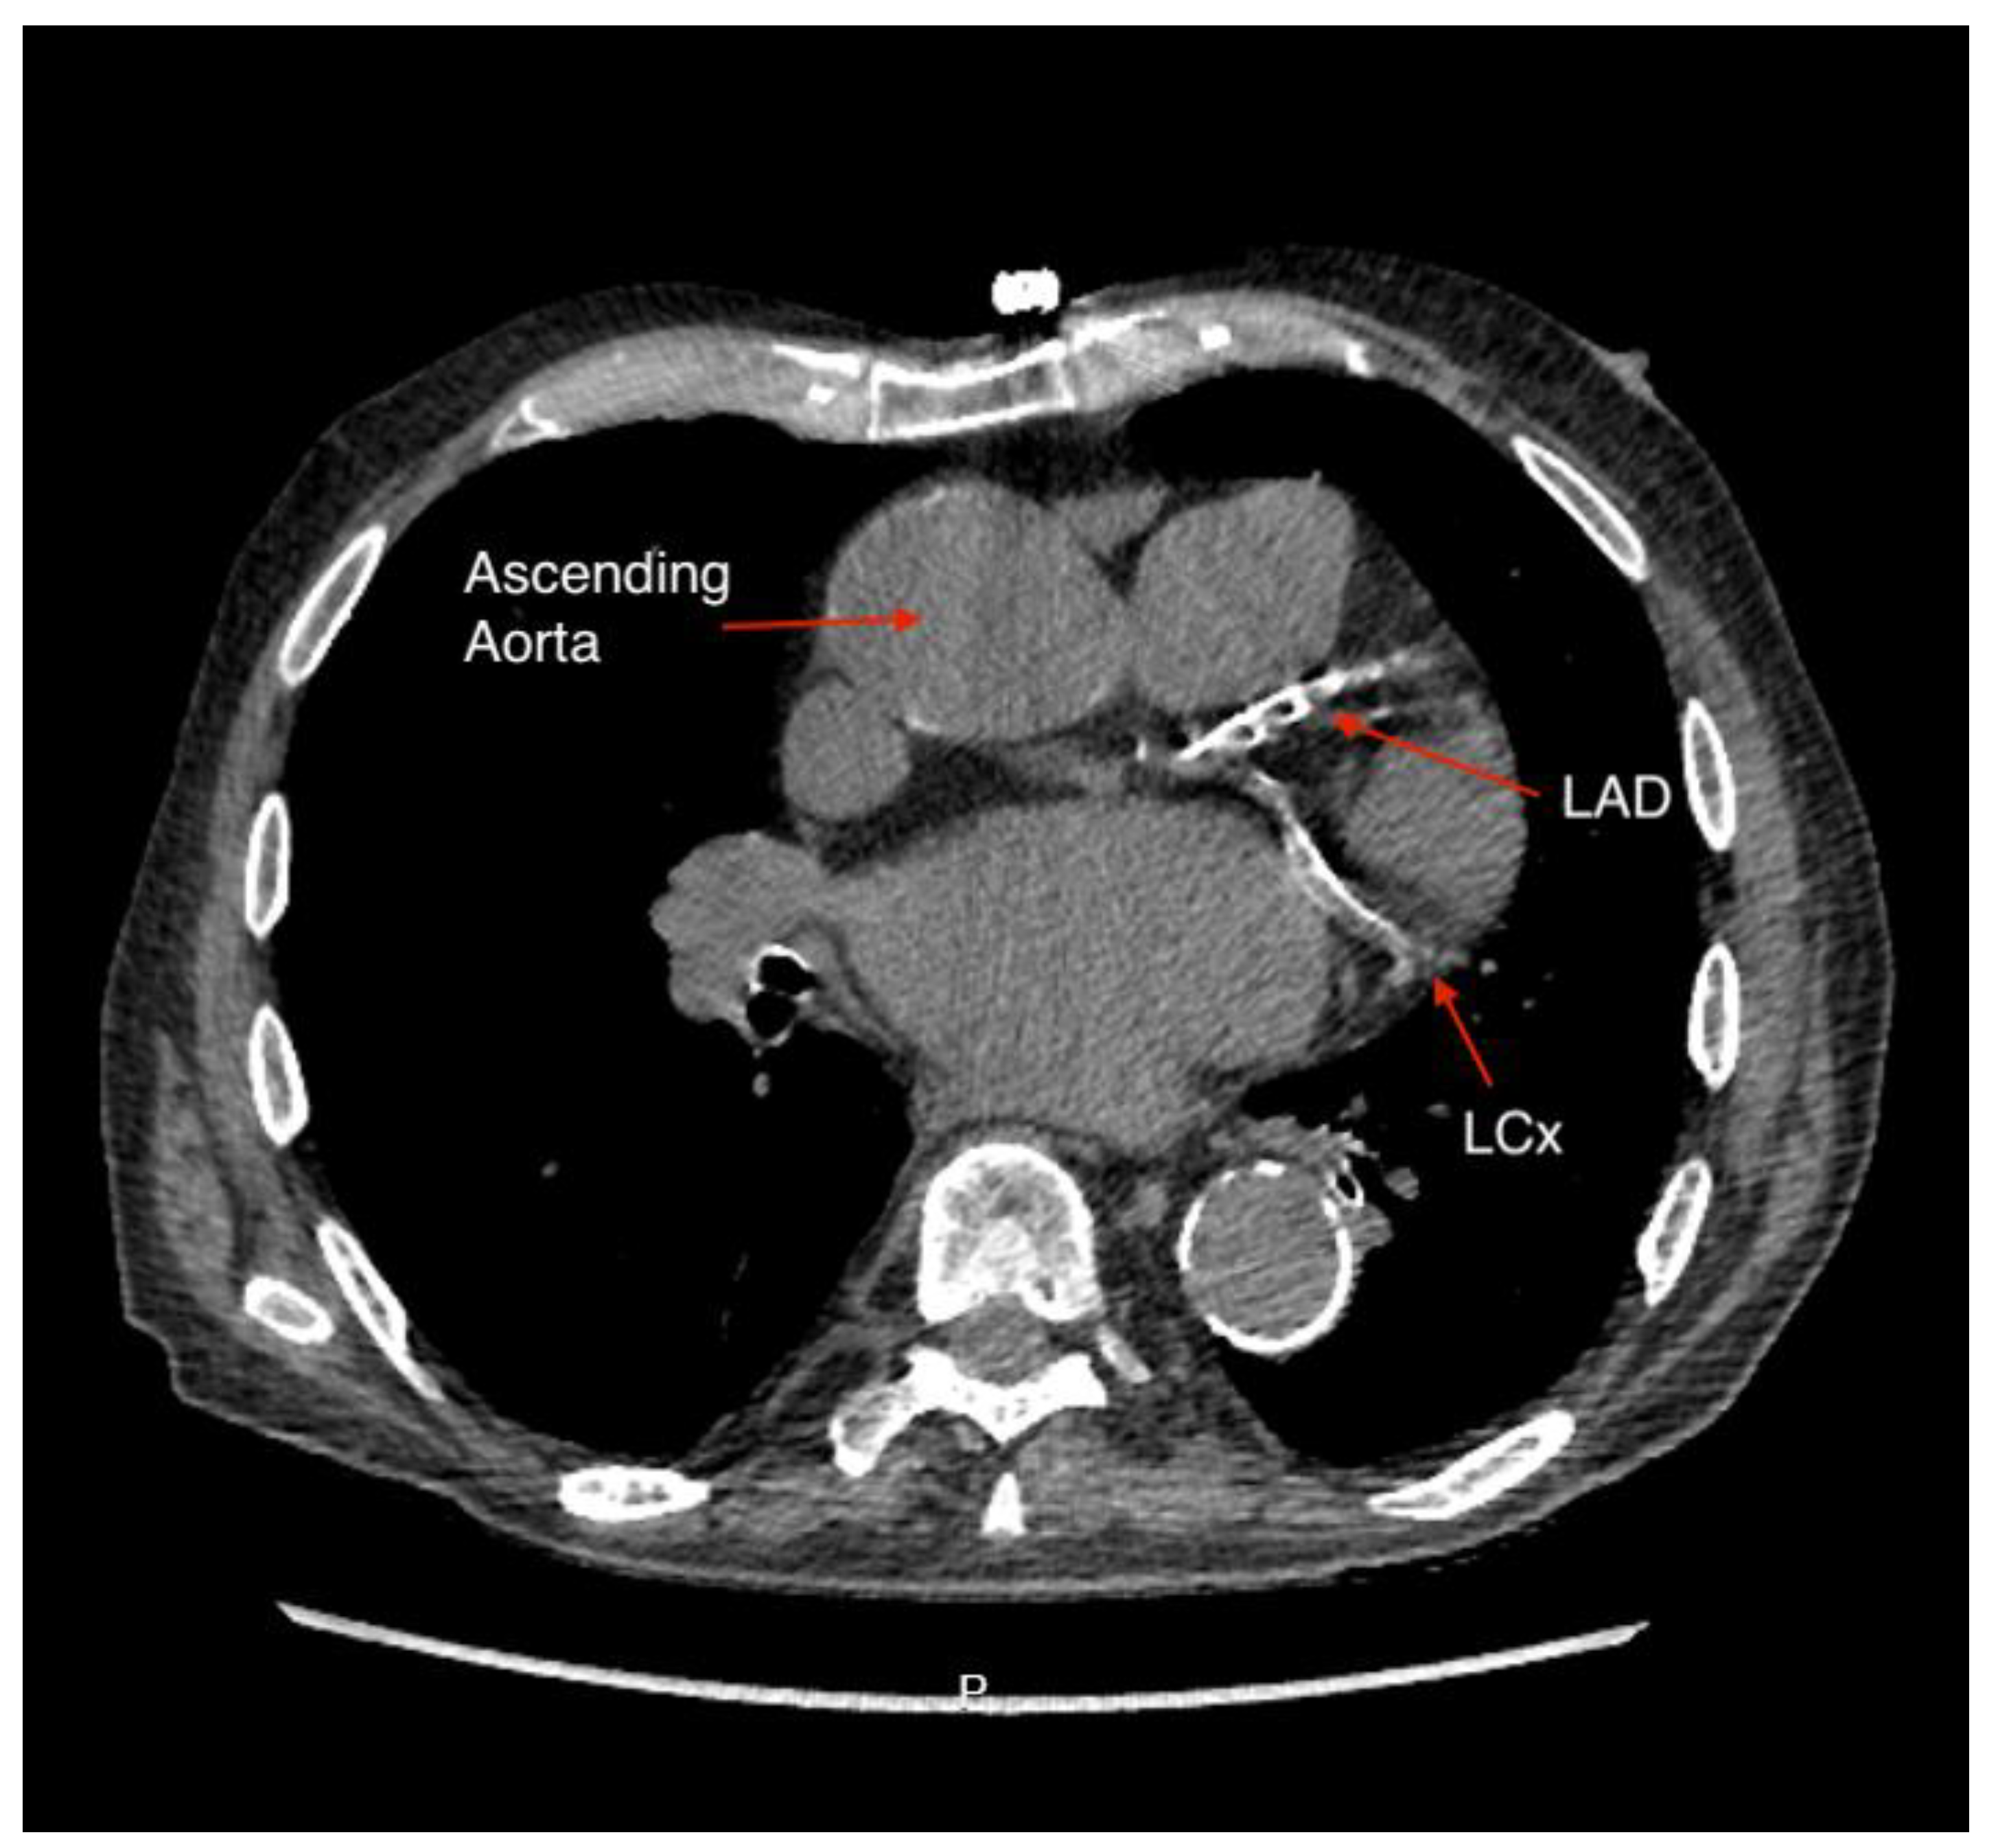

Figure 1. A non-gated CT scan showing severe calcification of the left anterior descending artery (LAD) and left circumflex artery (LCx).

Figure 1 shows heavily calcified coronary arteries on a non-gated CT scan.